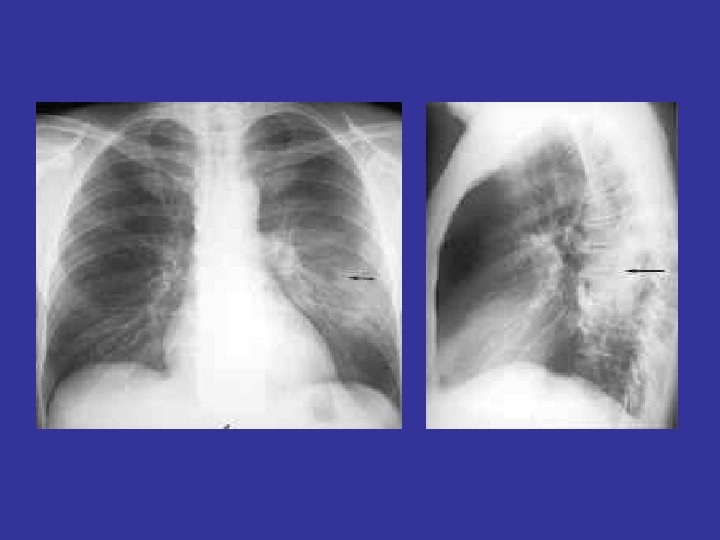

lateral view ? ! can detect otherwise hidden masses

The lateral chest film our best friend • Find abnormalities on the frontal film

The lateral chest film our best friend • Find abnormalities on the frontal film • Confirm abnormalities suspected from frontal film • Don’t be afraid to look at it